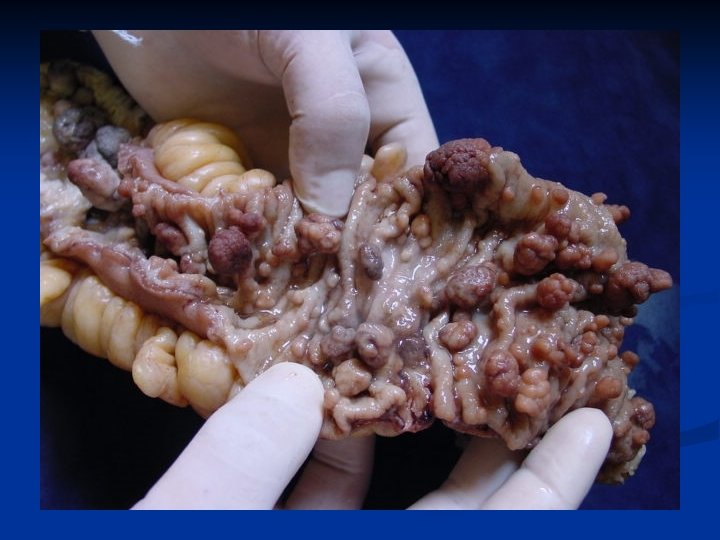

Familial adenomatous polyposis (FAP) n hereditary disease. The gene for FAP is on the long arm of chromosome 5 and is called the APC gene. There a lot of polyps / hundreds/ at the colon and rectal mucosa n very strong malignant potential n Diagnosis : colonoscopy, genetic tests

Familial adenomatous polyposis II. Treatment is surgical 1. colectomy + ileo-rectal anastomosis 2. total colectomy with permanent ileostomy ( cancer ) 3. „ restorative proctocolectomy“ - proctocolectomy with ileal pouch – anal anastomosis